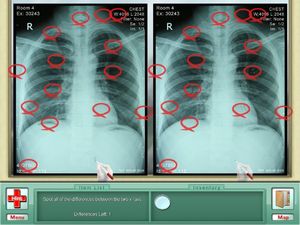

Unravel the Medical Mysteries in this Dramatic Puzzle Adventure! Follow Elizabeth through an engaging storyline with her fellow doctors, staff and some interesting sales reps.! Search for clues to diagnose and solve medical problems for a variety of patients in this enjoyable seek & find game. Study X-rays, blood tests and 4 more medical mini games add to the fun and future health of your patients.